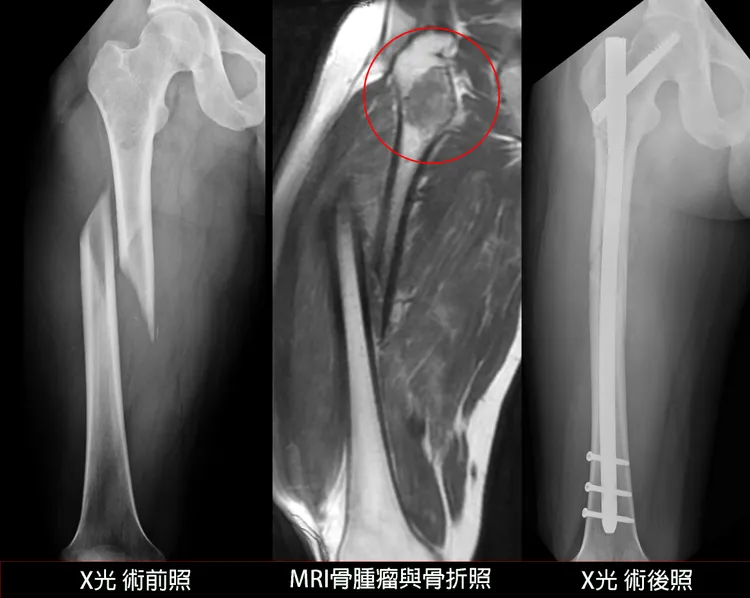

術前術後對照圖。光田提供

光田醫院骨科部楊鎮源部長表示,此案困難點在於,患者面臨嚴重骨折與性質不明的骨腫瘤,治療策略必須兼顧「確認骨腫瘤的良惡性」、「徹底清除骨腫瘤」與「骨折復位固定」,手術前會診放射科與病理科後制定計畫,一開始便針對骨腫瘤組織進行冰凍切片化驗。

所幸初步化驗結果證實腫瘤為良性,楊鎮源部長隨即將腫瘤組織徹底刮除,復位大腿骨折,並植入骨髓內鋼釘同時穩固骨腫瘤刮除後的空洞與骨折部位,透過跨科整合,一次性解決了原本複雜的雙重難題。一周後正式的病理報告證實是良性的纖維發育不全(Fibrous dysplasia),患者與家屬也終於可以放下心中的擔憂。